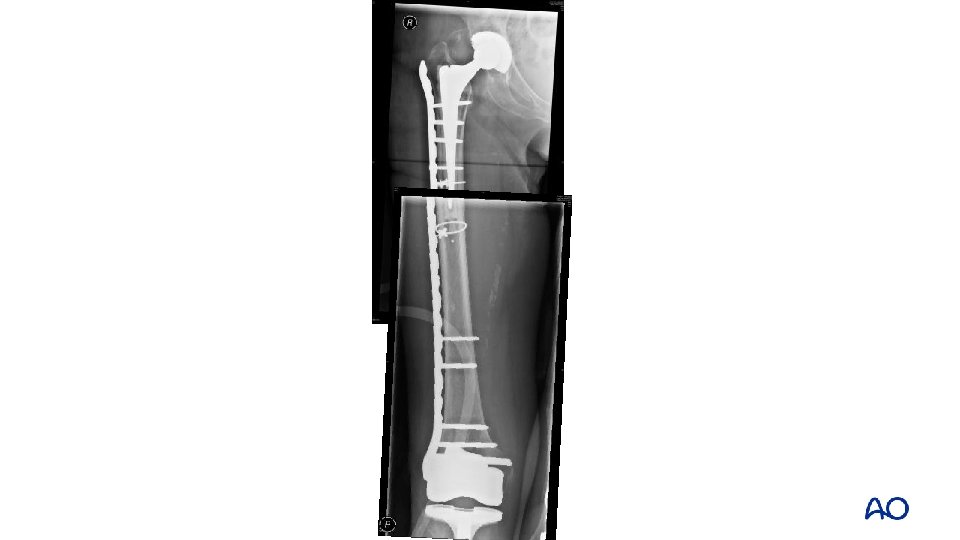

Failed rigid fixation • Biomechanical principles • Attempted absolute stability • Stress concentration at tip of prosthesis led to failure

Preoperative plan: option 1 • Relative stability • Create a long construct, trochanter to condyle avoiding stress concentration • Lateral locking plate

Preoperative plan: option 2 • Revision to a modular tapered, fluted stem • Aiming to achieve distal isthmic fixation with the stem • Reconstitution of the femoral tube proximally • +/- lateral plate

Option 2